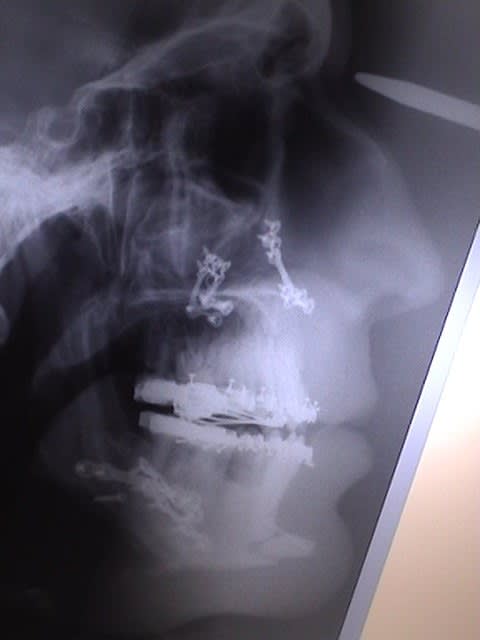

Il semble bien que la radio (et les coupes scan) que tu présentes appartiennent à un cas de traumatologie ou de chirurgie orthognathique. Ce ne sont certes pas des ancrages orthodontiques. Ne mélangeons pas tout, svp ! (à moins que ce ne soit de la provocation ou de la mauvaise foi, cher Bjc, mais je n'ose quand même pas penser cela de ta part).

Puisque j'ai eu la chance ( moi et non pas le patient) d'etre confronté à cette situation, je l'ai pris pour éxemple, pour montrer que ces techniques ne sont pas éxemptes de risques. Tout comme l'anesthésie intra-osseuse.

C'est un cas extrème, certes, mais ce sont les plus parlants.

Cas extrême ? J’ai mieux que cela (fig. jointes).

Ami d’Eugénol qui lis ces lignes, rassure-toi ! Ce sont des cas de chirurgie maxillo-faciale qui n’ont rien à voir avec les cas d’ancrages osseux orthodontiques, ni avec la discussion en cours. Notre bon Bjc a introduit cet aparté car il aime bien les facéties.